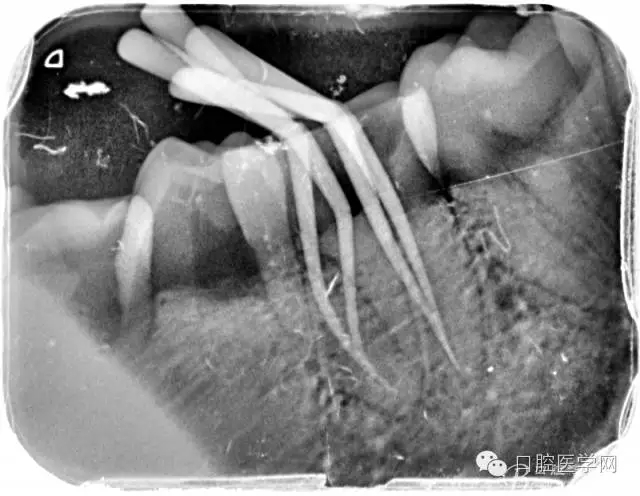

根管的解剖界限是从髓室根管入口到根尖部牙本质- 牙骨质交界处(生理性根尖孔) 。理想的根管充填应该是对生理性根尖孔冠方以上进行严密的三维封闭。临床上根据X线牙片判断根管充填的质量。牙片上充填材料与根管壁紧密接触一般被认为充填严密。关于充填止点,由于牙本质- 牙骨质界离根尖孔外表面平均距离为0. 5~0. 7 mm,同时相当多的根尖开口并不位于X线片的根尖处。因此临床上认为材料充填至距X线片牙根最尖端0. 5~1 mm (也有认为0. 5~2mm)为适填。

为达到更为理想的根充效果,研究人员和牙髓病医生一直在探索根管充填技术,并且发展出多种可供选择的方法。Ingle]将其归纳为3 类: ①“牙胶尖+封闭剂”式; ②“根尖1 /3充填”式; ③“注射或螺旋充填”式。目前临床广泛采用的主要是“牙胶尖+封闭剂”方式。按照充填压力的方向(侧向或垂直)不同和牙胶温度(冷或热)不同,根管充填有2 种基本技术:冷牙胶侧方加压充填和热牙胶垂直加压充填。现有的各种充填方法均是这2 种基本方法基础上的发展或改良。医生可根据方法的优缺点以及个人习惯选择使用。

6、封闭剂使用